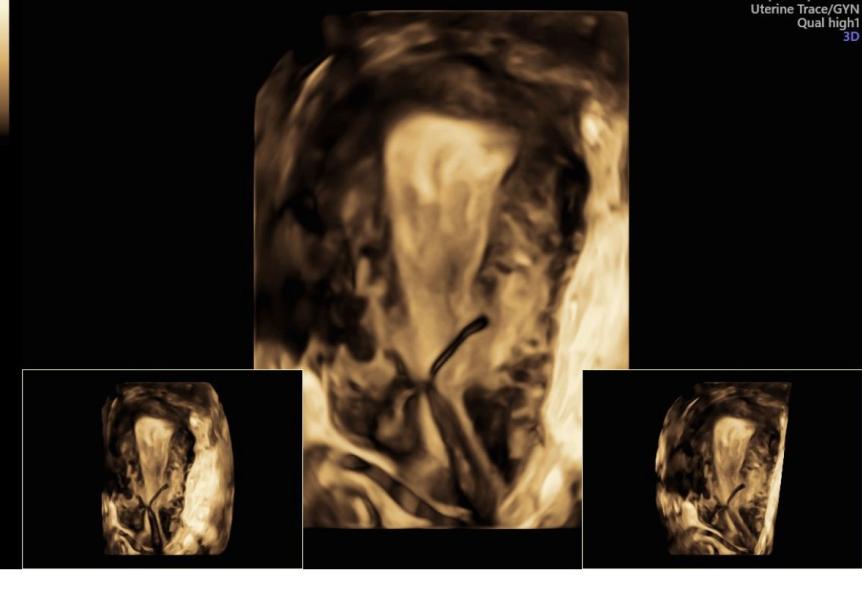

Мигрировала моя миреночка 😭

А она нам так была нужна для лечения гиперплазии 😣😔😔

Попробуем ее спасти , но процент небольшой . Риск , что выпадет - еще больше . Женщина рожала три раза .

Предполагая ваши вопросы - с помощью гистероскопа можно попробовать вернуть ее на место . Но не факт ,что получится.

Здесь был пересмотр через месяц после идеальной установки под контролем узи